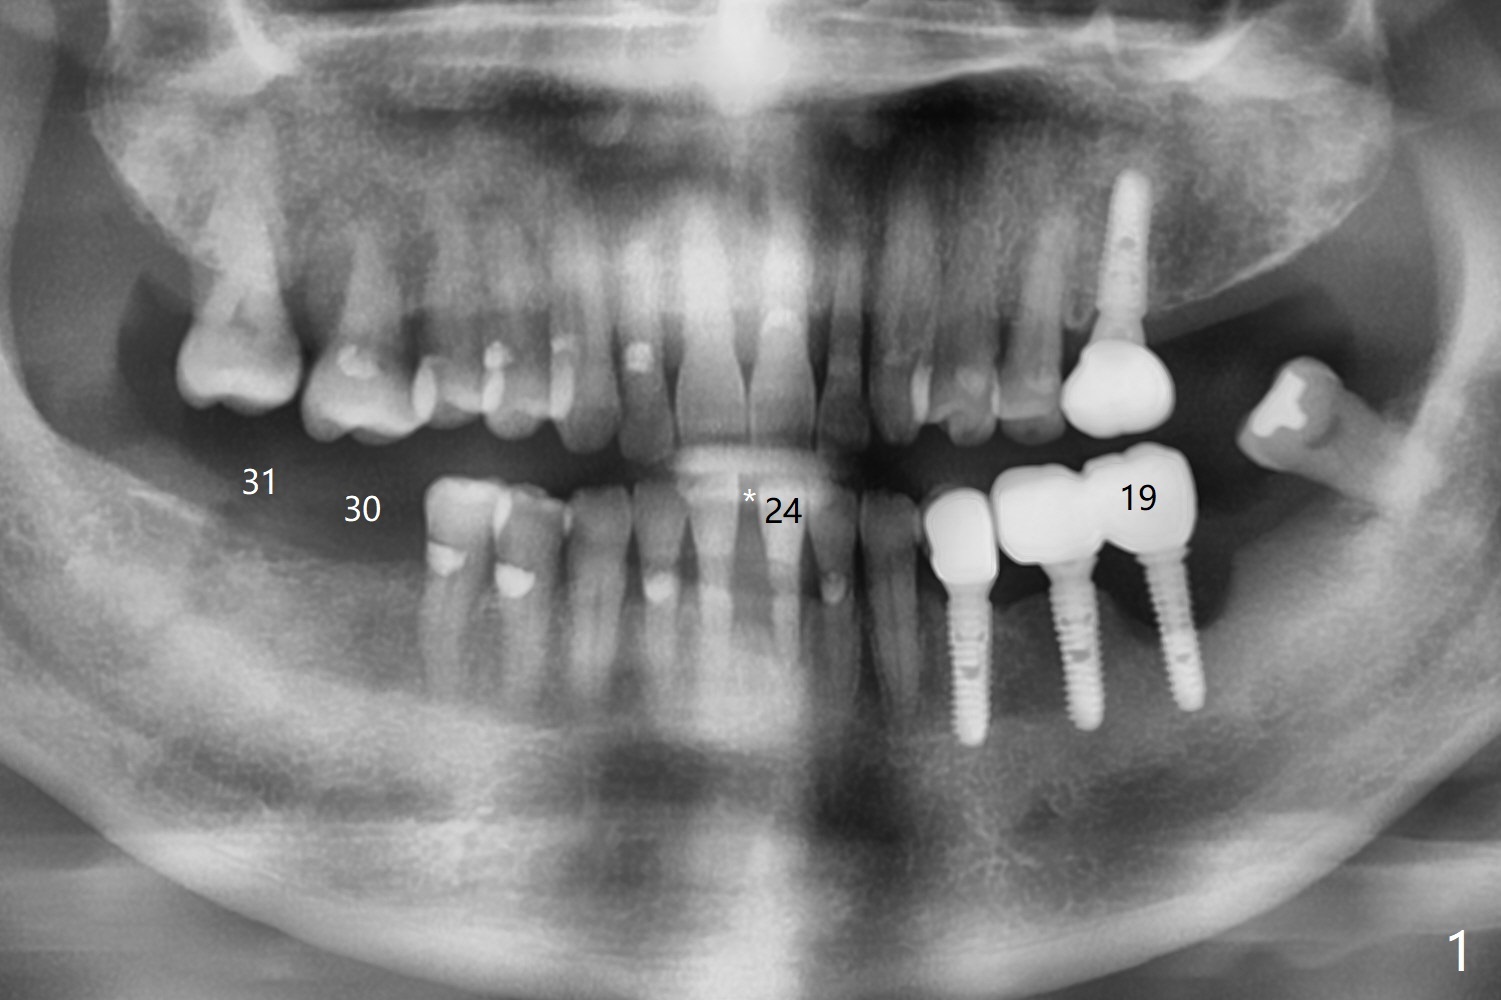

A 66-year-old man requests implant placement at #24, 30 and 31 (Fig.1). Bone loss at #19 and 24 lingual (Fig.2) suggests bruxism. The implant at #24 will be as buccal and mesial (to close the diastema between 24 and 25 (Fig.1 *)) as possible (Fig.2). The vertical space for restoration of 30 and 31 implants (Fig.3,4) is limited; the cusps of the opposing teeth may need to be trimmed.